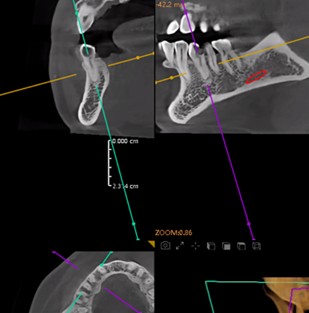

Preoperative Images

Secondary caries is present beneath the dental hard tissue. The residual tooth structure is fragile. Bifurcation is detected in the apical third of the root canal, with deviation of the root canal orifice. The long-term efficacy of root canal therapy cannot be guaranteed.